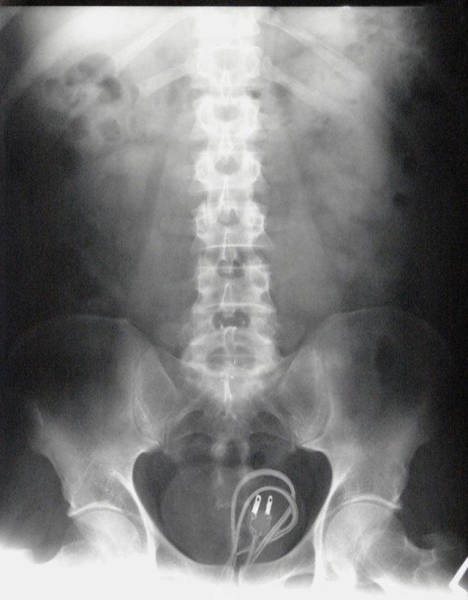

İÇİNDEKİ ŞEYE RÖNTGEN UZMANLARI ŞOK OLDU!

,Dünyada çekilen bu röntgenler hem röntgen uzmanlarını hemde görenleri şok ediyor...